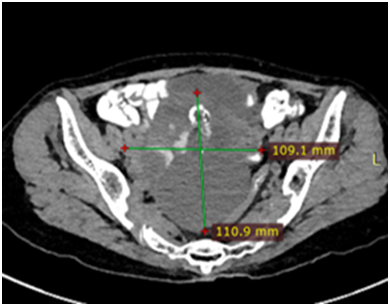

Ultrasound showed a large complex heterogenous pelvic mass likely to be ovarian malignancy. CECT Abdomen was done, which revealed a complex solid cystic lesion in pelvis (11x10x6cm) likely right ovarian malignant malignancy (Figure 1) with multiple heterogenous attenuating masses in liver suspicious of metastasis (Figure 2).

Figure 1 Complex pelvic mass of 11x10cm.